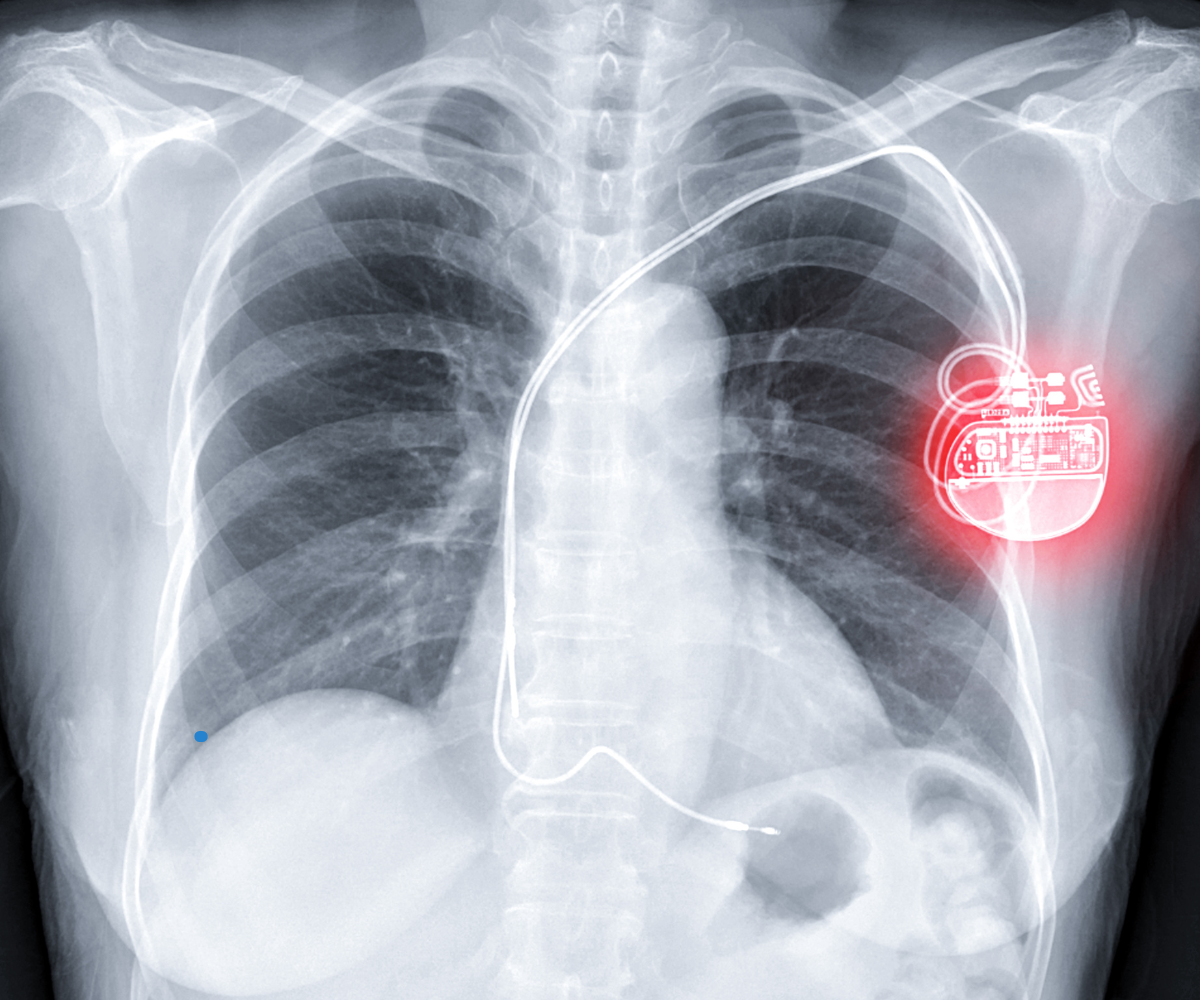

Pacemaker Installation

- Description: Implantation of a small device under the skin, typically near the collarbone, which sends electrical impulses to regulate the heart’s rhythm.

- Purpose: To treat bradycardia (slow heart rate) and other conditions where the heart’s natural pacemaker (the sinoatrial node) does not function properly.

Implantable Cardioverter Defibrillator (ICD)

- Description: A device implanted under the skin that monitors the heart’s rhythm and delivers electrical shocks if it detects dangerous arrhythmias like ventricular tachycardia or ventricular fibrillation.

- Purpose: To prevent sudden cardiac death by correcting life-threatening arrhythmias.